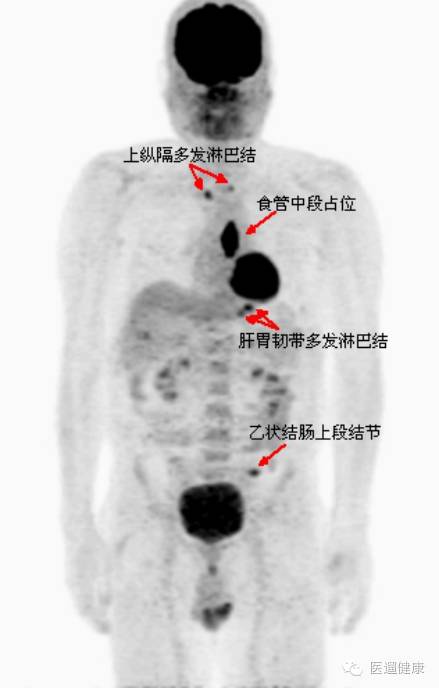

案例二、

呼吸科病例

病患:男,58岁。反复咳嗽咳痰10年,发热3周,入住呼吸科。

胸部CT:肺气肿,右肺上叶后段慢性炎症,

支气管镜:未见新生物,各管腔可见少量脓痰,以左肺上叶及右下叶背段为多。下一步怎么办?

↑

→

通过检查诊断出病患右肺上叶后段小斑片实变影,放射性轻度增高,SUV最大值约2.3。

鼻咽顶后壁、左鼻腔及右鼻腔鼻中隔处软组织增厚,左中、上鼻道软组织影填塞,左额窦、双筛窦、蝶窦、左上颌窦内软组织密度影填塞,SUV最大值约12.8。

脾脏增大,放射性普遍轻度增高,SUV最大值约2.8

该病例PET/CT影像诊断:

淋巴瘤病灶可能性大,建议活检协诊。

鼻咽部活检病理回报:(鼻腔新生物)大量坏死及少量粘膜,粘膜内异型的淋巴细胞浸润,瘤细胞表达:LCA(+),CD56(+),Vim(+),CD3(弱+),CD20(-),CD79α(-),CK(-),Ki67(60%+),

疑为NK/T细胞淋巴瘤,鼻型。